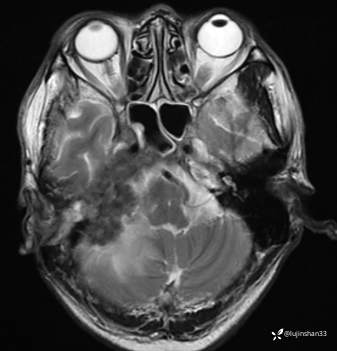

(2023-06-02 11:09,本院)磁共振(颅脑):1、右侧颞骨全切除术后改变,术区及相邻右侧斜坡、颞肌、咬肌、翼内外肌异常信号,考虑炎性肉芽肿性病变可能,请结合临床随诊复查;2、右侧小脑半球异常信号,考虑炎性病变可能;3、脑内散在缺血灶,软化灶形成;4、双侧蝶窦炎。

(2023-05-29 16:07,本院)CT颅脑:1、右侧颞骨全切除术后改变,术区见气体密度影,瘘管形成可能;术区多发软组织影,不完全除外炎性改变可能。2、左侧颞骨CT平扫未见明显异常。